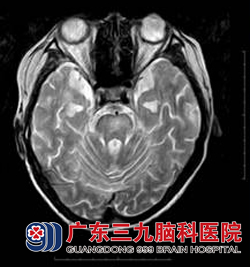

16岁的小志于1年前开始出现头晕、口角歪斜、流口水、言语不清、行走不稳、智力下降等症状。在当地医院按“大脑发育不全、颅神经功能障碍”予以药物治疗,效果不佳,近一个月以来症状进行性加重,为求进一步治疗于11月来到广东三九脑科医院神经内二科求诊。头颅磁共振检查发现其双侧基底节区、放射冠区、双侧侧脑室前角旁及脑干多发异常信号影,考虑脱髓鞘性病变可能性大(见图一),入院行相关检查,排除中枢神经系统感染、肿瘤等疾病,结合临床症状初步诊断为多发性硬化,予以激素冲击治疗1个月后复查头颅磁共振见原右侧放射冠区、中脑及桥脑病变内异常强化影已消失,桥脑及左侧基底节区病变范围较前缩小(见图二),患者吞咽困难、饮水呛咳、走路不稳等症状得以缓解;语言流利,肢体活动良好。www.999brain.com

图一:治疗前